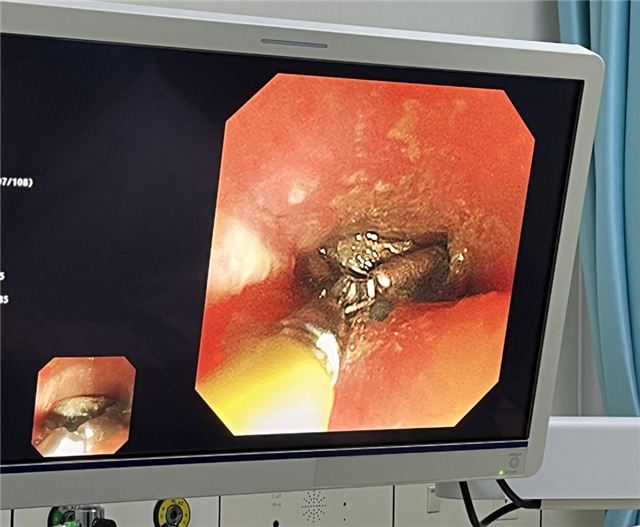

小小电池,大大麻烦 小孩子对世界充满了好奇,什么东西都喜欢放在嘴里尝尝,尽管家长一再谨慎看护,还是难免百密一疏。 …… 近日,长治市妇幼保健院儿内二科(儿童消化专科)接诊了一名10个月大的宝宝,宝宝的父母焦急万分,原来是宝宝误吞了纽扣电池!幸运的是,宝宝胸部X线片提示:纽扣电池位于食管上段狭窄处,暂未进入胃内。 要知道,一旦电池不能及时排出体外,体内液体将腐蚀电池外壳,致使电池中的电解液漏出,在体内发生化学反应,致使内脏灼烧、腐蚀而糜烂甚至穿孔等,不仅需要外科手术介入,更会对孩子造成不可逆的永久伤害! ❀ 误吞纽扣电池 “10个月大小的女宝宝因误吞纽扣电池已有2小时,需进行急诊内镜下取出。”当天,儿内二科主治医师郝旭东接到急诊电话通知。接到通知后,郝医生立刻警惕起来,因纽扣电池不同于普通的异物,极易造成食管、胃、肠等消化道损伤,严重者会危及生命,随即立刻请示儿内二科赵枫主任。考虑到患儿年龄小,并且风险较高,于是立刻通知麻醉科,做好手术相关准备。 时间就是生命,每提前争取1分钟,就可减少纽扣电池对患儿的损伤。郝医生在谈话间迅速与患儿家属沟通,告知其风险性、利害关系后,快速跑入内镜室,紧张的救治即刻开始。患儿胸部X线片提示纽扣电池位于食管上段狭窄处,10个月大的患儿不同于成年人,操作空间有限,加大了操作难度,儿内二科、麻醉科医生护士争分夺秒,在患儿全身麻醉下,采用无痛电子胃镜联合异物钳,顺利取出一枚直径1.5厘米的圆形纽扣电池。 警报虽然解除,但术中发现患儿食管粘膜后壁侧发黑、质脆,取出后可见患儿食管上段距门齿约12-16cm处后壁大范围电灼伤。郝医生考虑到,可能由于患儿呕吐导致电池短路引起食管损伤,可能出现感染、食管穿孔、水肿压迫气管影响呼吸、出血、食管气管漏等近期并发症,可能出现食管狭窄、吞咽困难等远期并发症。给予留置胃管,少量多次喂养,嘱咐患儿头高脚低体位,避免返流对症治疗。 2023年3月2日,为了解患儿恢复情况,儿内二科再次联合麻醉科采用无痛电子胃镜观察患儿食管壁情况,患儿食管壁恢复良好,办理出院。患者家属万分感激,专程来到儿内二科赠予一面锦旗。 ❀医生提醒: 误吞异物是医院急诊较常见的儿童意外伤害事件。家长要警惕“祸从口入”,孩子进食时切勿逗笑及呵斥孩子,加强高危物品的保管,尽量选择一体合成的玩具等。要高度重视误服电池的危害性,一旦发生儿童误服电池,应立即就医,尽快取出,不管电池有多小,都不要存在侥幸心理,避免给孩子造成更大的损伤。万幸的是,电池相对偏大,没有通过幽门进入小肠,且家长发现及时,电池仍然停留在胃里。否则,孩子将面临开腹手术! 带您走进儿内二科 儿童保健部儿内二科是以消化内科专业为特色的市级重点专科,是集临床、教学、科研于一体的临床业务科室,设有儿童重症监护病房,科室开放床位44张,专业技术人员26人,其中高级专业技术职称3人,硕士学位4人,专业队伍实力雄厚,拥有先进的儿童电子胃镜、儿童电子肠镜、儿童消化道CT等设备,儿童无痛胃肠镜检查和无痛胃镜取异物等技术居本地区领先水平。我院开展的检查项目有:幽门螺杆菌检测、乳糖不耐受检测、胃食道PH检测、消化道病原检测等。目前诊疗的疾病有:儿童反复呕吐、胃食管反流病、急慢性胃炎、消化性溃疡、急慢性腹痛、腹泻等常见病多发病;对先天性幽门肥厚/狭窄、消化道出血、消化道息肉、胰腺炎、婴儿肝炎综合征、肝功能衰竭、炎症性肠病、坏死性小肠炎、腹膜炎等疑难病症的诊疗方面积累了丰富的经验。本着“仁心善术、惠泽妇儿”的精神,竭诚为广大儿童服务。 专家简介 赵枫 长治市妇幼保健院小儿消化内科主任,主任医师,长治医学院兼职副教授,为“山西省百千万卫生人才骨干精英人才”、“长治市学科技术带头人”。兼任华北地区儿科学组常务委员、长治市新生儿学组副主任委员、山西省医学会儿科分会重症学组副组长、 国家级住院医师规范化培训师资等,发表国家级、省级论文数十篇。曾在美国旧金山太平洋医疗中心研修,先后在北大一院,北京儿童医院,山西省儿童医院进修学习。擅长儿童消化系统、呼吸系统、神经系统及危重症疾病的诊治。 出诊时间:每周三、日上午;周五下午 郝旭东 主管医师,中共党员,长治市妇幼保健院儿科医师,兼任中国妇幼保健协会小儿消化微创学组全国青年委员、中国医师协会儿科医师分会儿童消化内镜学组委员。擅长小儿消化道疾病的诊治,以及儿童胃镜、肠镜的操作,在长治地区率先开展儿童胃肠镜检查及诊疗技术。 出诊时间:每周一至周五下午 咨询电话: 0355-2052654 部分图片来源于网络,如有侵权,请联系删除 供稿 | 儿内二科 贺东伟 审核 | 儿内二科 赵枫 编辑 | 宣传科 王慧丽 排版 | 实习生 潘文华 请长按二维码关注,获取更多妇幼资讯